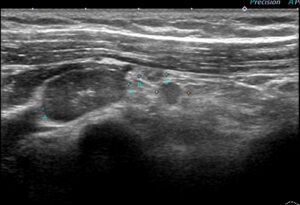

大きなレベルⅡは、レベルⅢに近い部位までせり出し、その奥(図中央)にはレベルⅢが

確認できる。

←外側 (皮膚側) 内側(奥)→

これらエコーをつなぎ合わせたもの

リンパ節は黄色に表現

大胸筋(茶色)の裏に小胸筋(こげ茶色)

大胸筋の外側にリンパ節2つ、大胸筋の裏にリンパ節1個 これら3個がレベルⅠ

小胸筋裏にリンパ節(これが最大で2㎝)これがレベルⅡ

それより内側(奥)に比較的小さいリンパ節2個 これらがレベルⅢ

色分けすると 赤とオレンジ:レベルⅠ、 黄色:レベルⅡ 、赤(周囲に点線の小さいもの):レベルⅢ